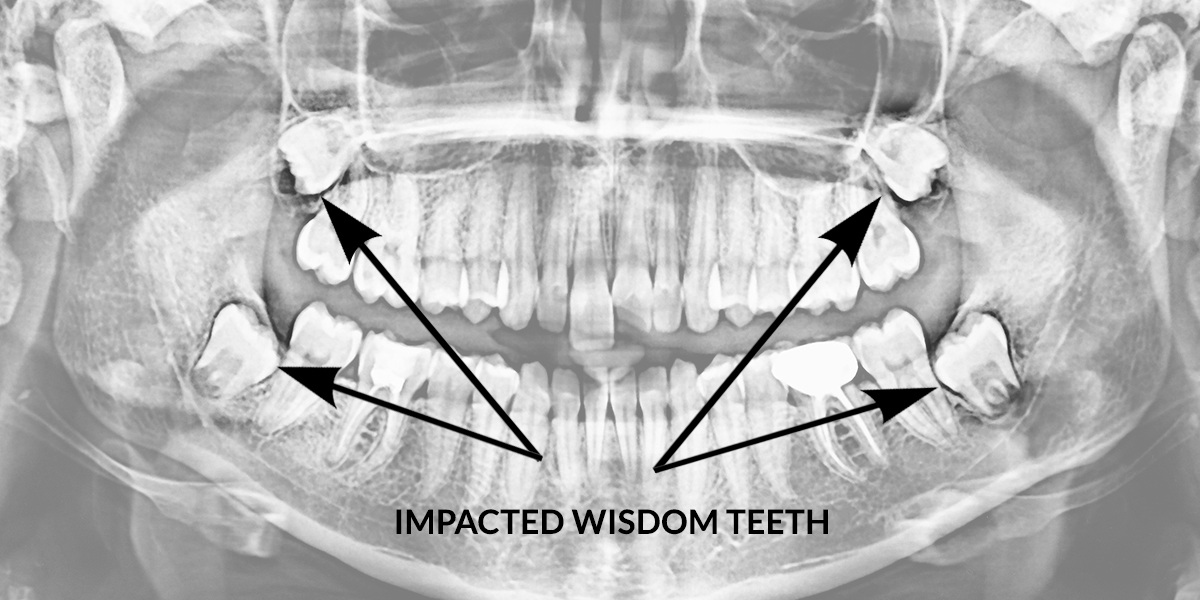

An X-ray Showing Impacted Teeth Growing Irregularly On Both Ends Of The

Panoramic Xray Showing Impacted Wisdom Teeth Stock Photo 1273167061

www.shutterstock.comImpacted Teeth Hi-res Stock Photography And Images - Alamy

www.shutterstock.comImpacted Teeth Hi-res Stock Photography And Images - Alamy

www.alamy.comimpacted ray teeth tooth fully